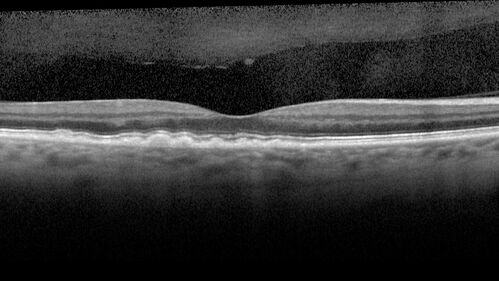

Large and Extensive Macular Drusen

64 year old female with 20/25 vision taking vitamins in for a checkup.